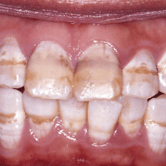

Fluorosis dental

La fluorosis dental es una alteración en el esmalte de los dientes causada por la ingesta excesiva de flúor durante el desarrollo dental.

Los padres pueden notar manchas blancas o marrones en los dientes de sus hijos. Aunque la fluorosis no afecta la salud dental, puede causar preocupaciones estéticas.

Es importante controlar la cantidad de flúor que los niños ingieren para prevenir esta condición.

Hipoplasia del esmalte

La hipoplasia del esmalte es un desarrollo defectuoso del esmalte dental, que puede causar manchas, surcos o áreas delgadas en los dientes.

Los padres pueden notar dientes con manchas blancas o marrones, y superficies ásperas. Esta condición puede aumentar el riesgo de caries y sensibilidad dental.

El tratamiento puede incluir selladores dentales y restauraciones para proteger los dientes afectados.